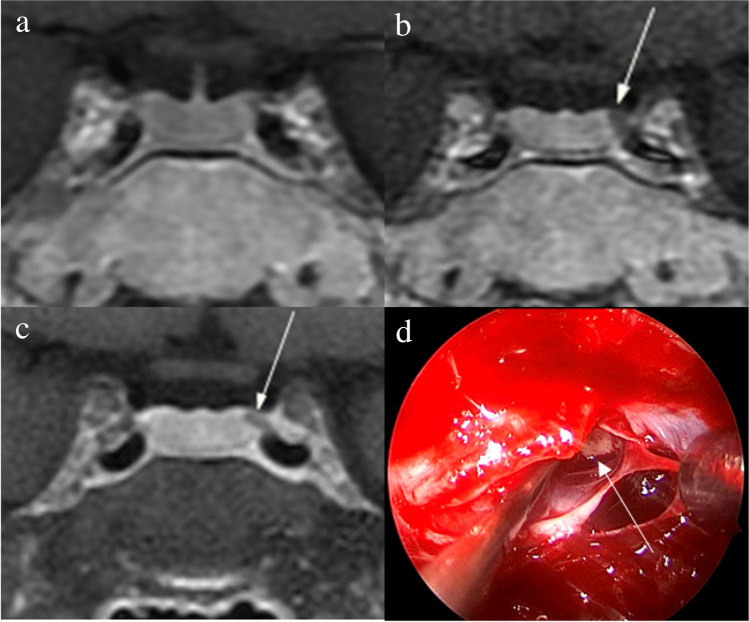

Figure 2 shows that a 5-mm pituitary microadenoma was identified on preoperative pituitary MRI. The margin of the lesion was fully delineated on hrMRI, but not on cMRI and dMRI. Figure 3 shows that a 3-mm pituitary microadenoma was missed on cMRI, but identified on dMRI and hrMRI. Figure 4 shows that a 5-mm pituitary microadenoma was correctly diagnosed on hrMRI, but missed on cMRI or dMRI. Figure 5 shows that a 4-mm pituitary microadenoma was evident on coronal images as well as reconstructed axial and reconstructed sagittal images on hrMRI.

Fig. 3.

Images in a 34-year-old woman with Cushing’s disease. No tumor is identified on (a) coronal contrast-enhanced T1-weighted image obtained with two-dimensional (2D) fast spin echo (FSE) sequence. The 3-mm pituitary microadenoma (arrow) with delayed enhancement is identified on the left side of the pituitary gland on (b) coronal dynamic contrast-enhanced T1-weighted image obtained with 2D FSE sequence and (c) coronal contrast-enhanced T1-weighted image on high-resolution MRI obtained with 3D FSE sequence. d Intraoperative endoscopic photograph during transsphenoidal surgery shows a 3-mm pituitary microadenoma (arrow)